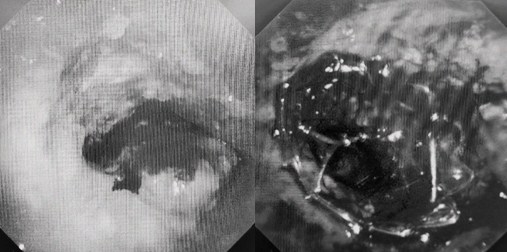

時(shí)間就是生命!了解患者病情后,歐陽(yáng)海峰立刻啟動(dòng)氣道梗阻緊急救治通道,協(xié)調(diào)院前轉(zhuǎn)運(yùn),急診快速入院流程。凌晨患者入院胸部CT顯示,現(xiàn)存唯一的呼吸通道在右主支氣管處,狹窄處僅約3毫米,患者命懸一線!

運(yùn)用呼吸介入技術(shù),軟硬鏡結(jié)合快速開通氣道,是患者目前唯一可行的治療方案,手術(shù)刻不容緩!但存在麻醉后氣道完全塌陷閉合、大出血、窒息等巨大風(fēng)險(xiǎn)?;颊叽饲敖舆B轉(zhuǎn)診3家醫(yī)院,均建議保守支持治療或轉(zhuǎn)院。歐陽(yáng)海峰詳細(xì)了解患者病史,全面評(píng)估影像檢查結(jié)果后,決定盡快進(jìn)行手術(shù),組織醫(yī)護(hù)團(tuán)隊(duì)對(duì)患者進(jìn)行持續(xù)密切監(jiān)測(cè),充分保障其術(shù)前安全。

患者入院第二天,在麻醉手術(shù)中心全力配合下,歐陽(yáng)海峰帶領(lǐng)呼吸介入團(tuán)隊(duì),歷時(shí)40分鐘快速置入硬質(zhì)支氣管鏡、鏟切腫瘤,并順利植入全覆膜TTS支氣管金屬支架?;颊邭舛贪Y狀即刻緩解,為患者贏得了寶貴的后續(xù)治療機(jī)會(huì)。